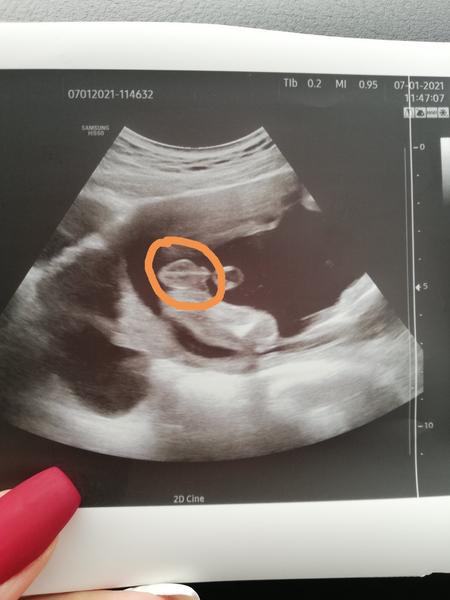

Holka nebo kluk? Prosím o názor 🙏🏻❤️

Obracím se k vám o názor ohledně ultrazvuku sem teď ve 20tt+2 dnes sem byla u paní doktorky..

Kde mi řekla že to vypadá asi na kluka.. Jenže minulou návštěvu řekla že to asi vypadá na holku 🤦🏻♀️

Tak sem celkem zmatená a nevím co si myslet vidíte tam něco? 🍀🙏🏻 Děkujuuu

@nikolaa123 řekla bych, že to jsou kulky 😁